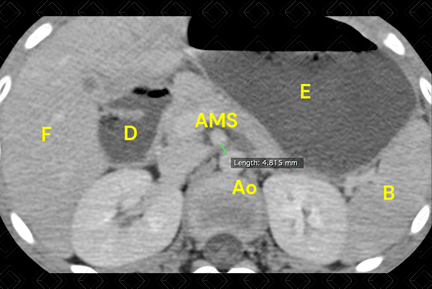

Texto alternativo para a imagem Figura 2. Créditos: Dra. Elazir Mota - Rio de Janeiro/RJ

Descrição da figura 2: Distância aortomesentérica, medida no plano axial, inferior a 8 mm.

• Tomografia computadorizada do abdome: D iante desta suspeita, deve sempre ser realizado após a administração do contraste venoso. Existem dois indicadores tomográficos da síndrome que são o ângulo aortomesentérico inferior a 22 graus, medido no plano sagital (figura 1 ) e a distância aortomesentérica, medida no plano axial, inferior a 8 mm (figura 2) . Além disso, observa-se distensão da primeira e segunda porções duodenais, bem como do estômago.